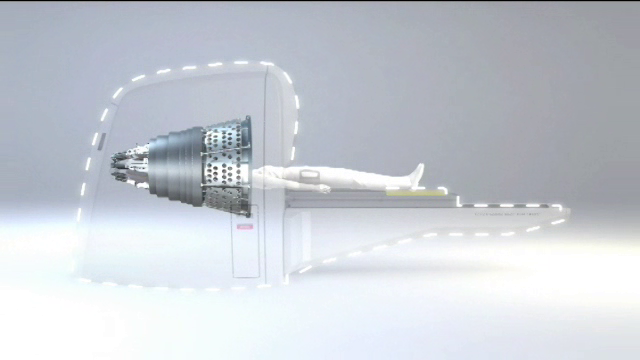

Περιγραφή της θεραπείας Η θεραπεία με γ-knife πραγματοποιείται κατά κανόνα σε μία συνεδρία. Το πρωί της θεραπείας στερεώνεται στο κεφάλι του ασθενούς ένα τετράγωνο μεταλλικό πλαίσιο από τιτάνιο. Η στερέωση γίνεται με τέσσερεις καρφίδες οι οποίες τοποθετούνται υπό τοπική αναισθησία. Ο ασθενής υποβάλλεται σε μαγνητική ή/και αξονική τομογραφία εγκεφάλου (και ψηφιακή αγγειογραφία στις αρτηριοφλεβώδεις δυσπλασίες) με το μεταλλικό πλαίσιο. Ακολουθεί ο σχεδιασμός της θεραπείας σε εξειδικευμένο σύστημα υπολογιστών με την συμμετοχή και έγκριση ακτινοθεραπευτή και ακτινοφυσικού. Το πλάνο θεραπείας εξάγεται ηλεκτρονικά στο ρομποτικό σύστημα γ-knife και ο ασθενής τοποθετείται στο μηχάνημα. Η κεφαλή του ασθενούς παραμένει ακινητοποιημένη κατά την διάρκεια της θεραπείας (το μεταλλικό πλαίσιο εφαρμόζει σε ειδική υποδοχή). Η θεραπεία είναι αθόρυβη, ο ασθενής δεν αντιλαμβάνεται τίποτα από αυτήν και διαρκεί από 30 λεπτά έως μερικές ώρες. Μετά το πέρας της θεραπείας αφαιρείται το μεταλλικό πλαίσιο από το κεφάλι του ασθενούς, ο οποίος παραμένει στο νοσοκομείο μερικές ώρες έως και 1 ημέρα. |